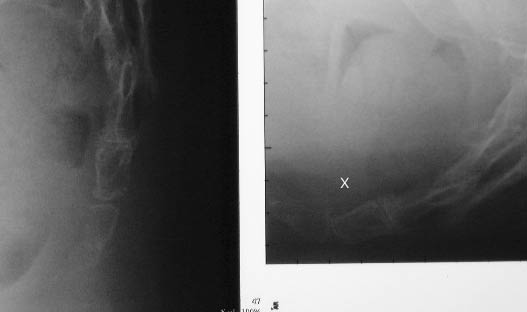

Case #9. Another example of misalignment in flexion (X).